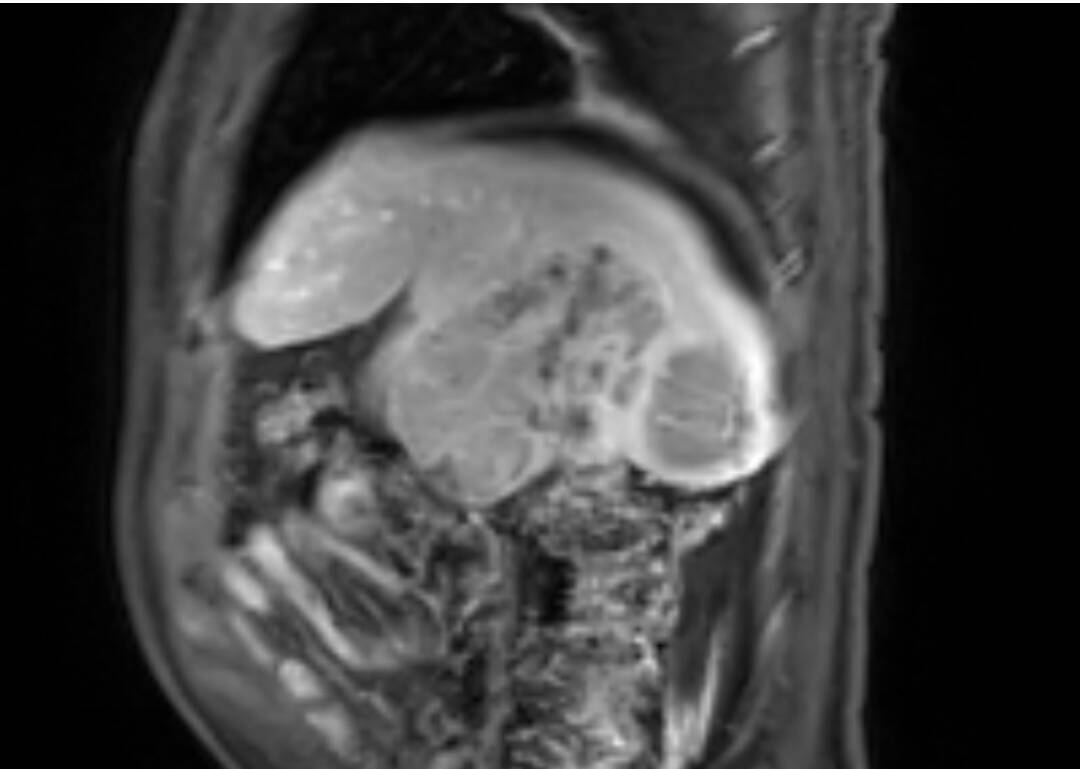

其中,成功为一名患者实施超大肝癌切除术,完整切除肿瘤大小达19cm×15cm,精准突破肝胆外科传统“手术禁区”,标志着普外二科在复杂肝胆肿瘤外科治疗领域迈上全新台阶。

此次切除的肿瘤体积巨大、血供丰富,与肝内重要血管、胆管粘连紧密,术中极易发生大出血、胆漏、肝功能衰竭等致命并发症。手术既要确保肿瘤完整根治、切缘干净,又要最大限度保留正常肝组织,难度与风险远超常规肝癌手术,对团队技术、经验与协作能力提出极高要求。

术前,科室联合影像、麻醉、重症监护、护理等多学科团队开展MDT会诊,全面评估肿瘤位置、大小、浸润范围及患者基础状况,精准规划切除路径与血管保护策略,反复推演手术流程,制定周密手术方案与应急预案,为手术成功筑牢坚实安全防线。

术中,手术团队在胡三元特聘专家与赵承乾科主任指导下,凭借精湛外科操作与丰富临床解剖经验,在高清手术视野下精细分离、逐层剥离、精准控切,妥善保护肝门部血管、胆管等关键结构,平稳完整剥离并切除巨大肿瘤,全程出血少、创伤可控,顺利完成高难度根治操作。